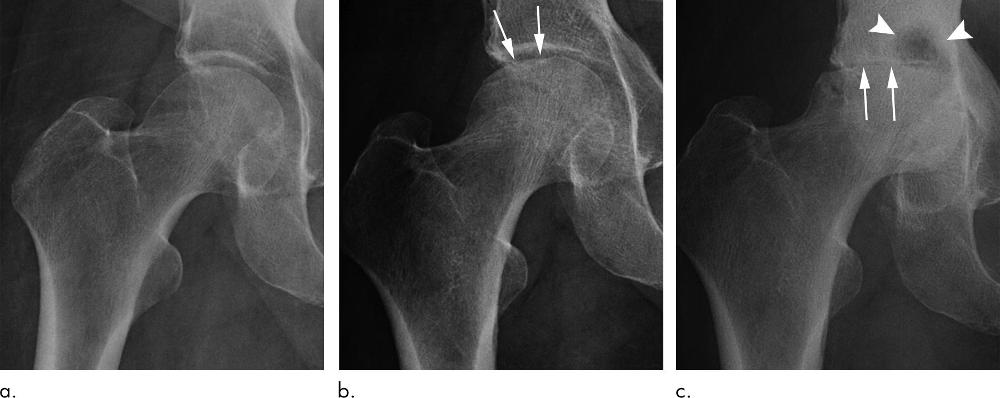

Figure 5. Rapid progressive osteoarthritis (RPOA) type 2 in an 81-year-old woman with right hip pain who was referred for right hip intra-articular corticosteroid injection. (a) Anteroposterior right hip radiograph shows no definite osteoarthritis. (b) Within 3 months after receiving the injection, this patient presented with worsening right hip pain. Repeat anteroposterior right hip radiograph shows subchondral insufficiency fracture, with collapse of the superior femoral head articular surface (arrows). (c) Pain increased markedly over the following month, and this repeat anteroposterior right hip radiograph shows bone loss and destruction of the femoral head with severe joint space loss, consistent with RPOA type 2 (arrows). In addition, there are extensive cystic changes at the acetabulum (arrowheads).